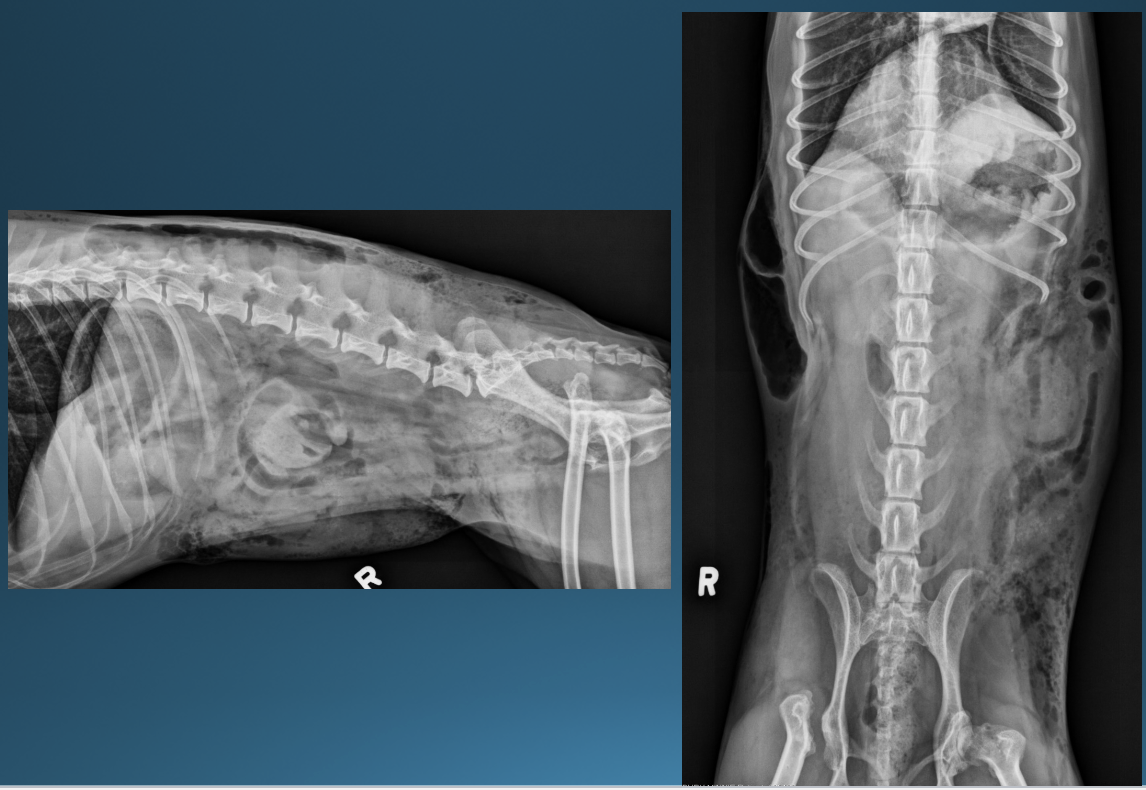

What is shown in these images?

normal abdomen and normal body wall in a dog